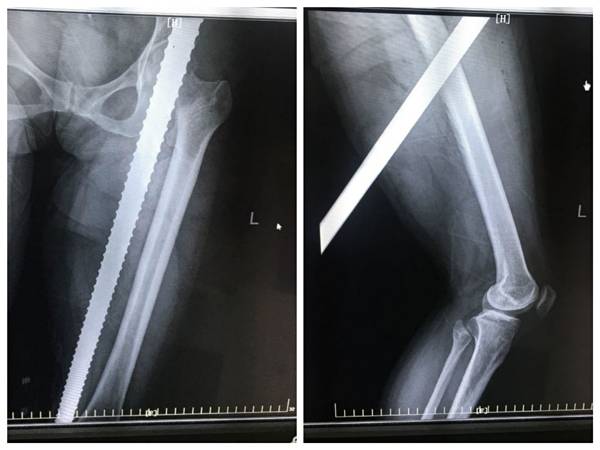

46岁的患者李女士,在工地干活时不慎被坠落的钢筋刺穿右侧大腿,受伤后流血不止,被工友紧急送至二一五医院,经检查发现,只见患者右侧大腿中段可见直径18mm的钢筋自大腿上段前侧刺入,下段后内侧穿出,触目惊心,情况非常危急。

时间就是生命,骨二科接诊大夫立即通知郭永良主任,并紧急完善相关术前检查,开通绿色通道,积极联系麻醉科与手术室,做好术前准备。郭永良主任、王争刚副主任医师查看病人后。果断指示行急诊手术行钢筋取出血管神经探查术,手术中经探查发现钢筋距离股动脉的距离仅0.5cm,十分危险。术中小心仔细分离并保护好血管、神经后,行钢筋取出清创缝合术,手术成功。此时,距离患者入院仅用时125分钟。